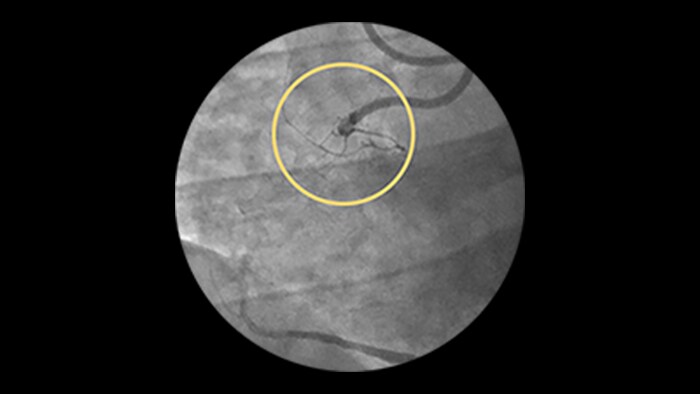

70% reduction in all-cause mortality out to 3 yrs57